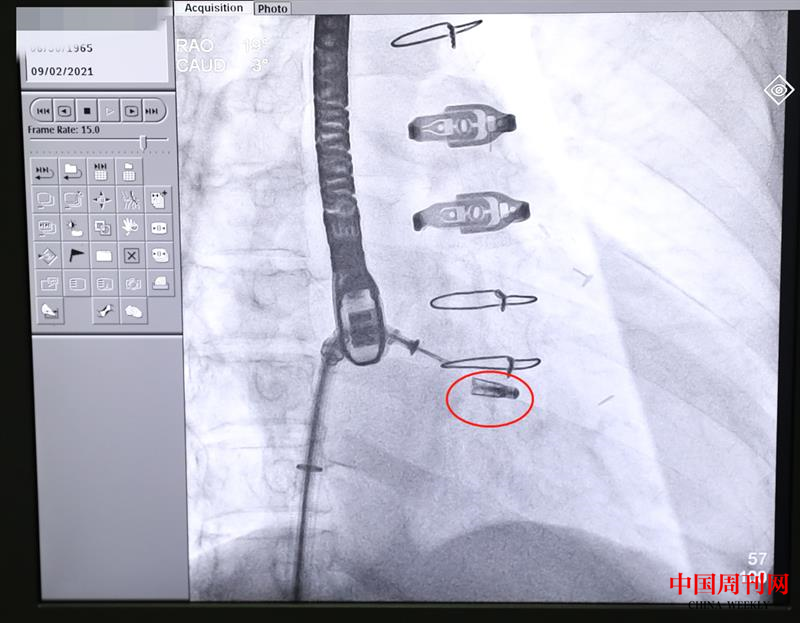

9月2日上午,在完成充分的術(shù)前準(zhǔn)備和預(yù)案工作后,中大醫(yī)院心血管內(nèi)科、麻醉科、胸心外科等組成聯(lián)合保障團隊。在麻醉科醫(yī)生成功實施全麻后,心血管內(nèi)科馬根山主任醫(yī)師、丁建東主任醫(yī)師、陳立娟主任醫(yī)師、徐榮豐主治醫(yī)師等開始施行介入手術(shù),在食道超聲和醫(yī)學(xué)影像設(shè)備的引導(dǎo)下,手術(shù)專家經(jīng)皮穿刺,借助先進的微創(chuàng)導(dǎo)管輸送系統(tǒng),通過逐級擴張鞘將可操控導(dǎo)引導(dǎo)管送入左心房,引導(dǎo)二尖瓣夾導(dǎo)管輸送系統(tǒng)進入左心房;接著在左心房調(diào)整二尖瓣夾的位置。由于該患者病變復(fù)雜,二尖瓣夾閉的難度很大,相當(dāng)于患者的二尖瓣上有個大口子,需要用一個夾子把二尖瓣的前瓣和后瓣夾起來,達到減輕反流的目。介入專家團隊在手術(shù)過程中反復(fù)調(diào)整、多次探討,最終成功夾合前后瓣的部分瓣葉,使之貼合在一起。經(jīng)超聲及醫(yī)學(xué)影像造影檢查證實,二尖瓣夾已夾緊,患者反流癥狀明顯減輕,最終釋放夾子,撤回輸送系統(tǒng),完成修復(fù)手術(shù)。術(shù)后,張先生的癥狀顯著改善,目前,正在接受進一步觀察治療。